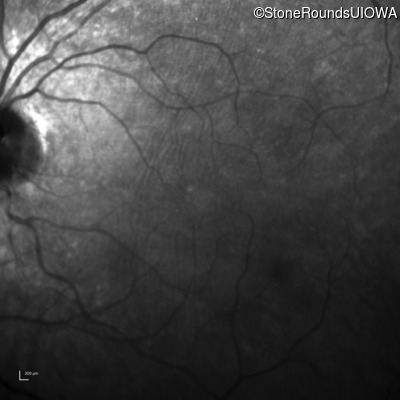

Infrared Fundus Photograph - Left - 20/50 -1

Exemplar